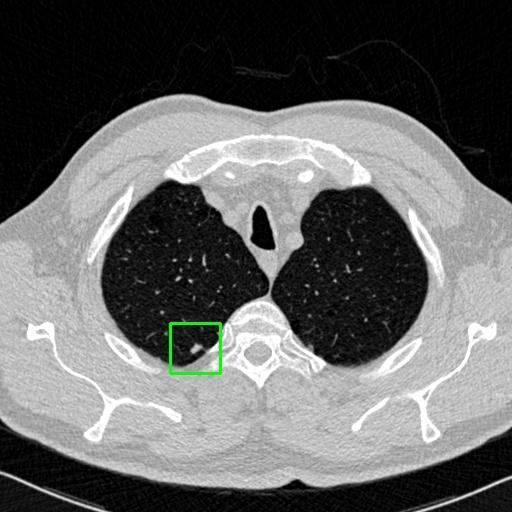

We developed an AI-based system using deep learning models for analyzing lung CT scans to detect and classify pulmonary nodules. We chose the YOLOv11 architecture for its enhanced object detection capability and adapted it specifically for medical imaging, incorporating pixel-level precision and severity classification.

Classification into three severity levels with colored bounding boxes.

Maintaining performance on small, complex features like micro-nodules tested the limits of traditional object detectors.

Designed a severity classification system that categorizes nodules into null, moderate, and severe using colored bounding boxes, assisting in rapid clinical decision-making.